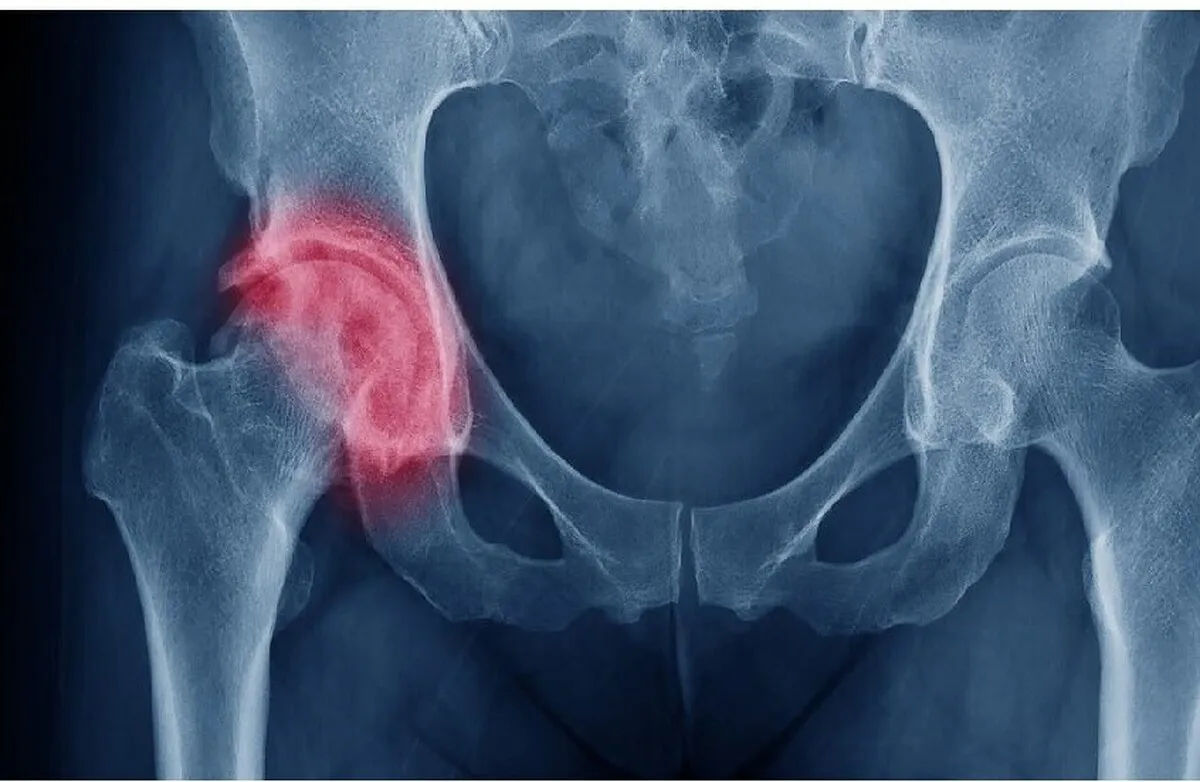

أعلنت شركة "روستيخ" الحكومية أن خبراء المعهد المركزي لجراحة العظام والكسور التابع للشركة ابتكروا منظومة داخلية لعلاج المفاصل التالفة.

وقد أجرى الجراحون الروس أول عملية ناجحة استغرقت ثلاث ساعات، لتركيب مفصل ورك صناعي واستعادة بناء عظم الفخذ والحق (تجويف صغير في عظم الورك) باستخدام الابتكار الروسي.

وتتكون المنظومة الداخلية المبتكرة من طرف اصطناعي مصنوع من التيتانيوم وعناصر إضافية للتعويض عن عيوب العظام، ما يضمن التثبيت الموثوق والتكامل مع النسيج العظمي.